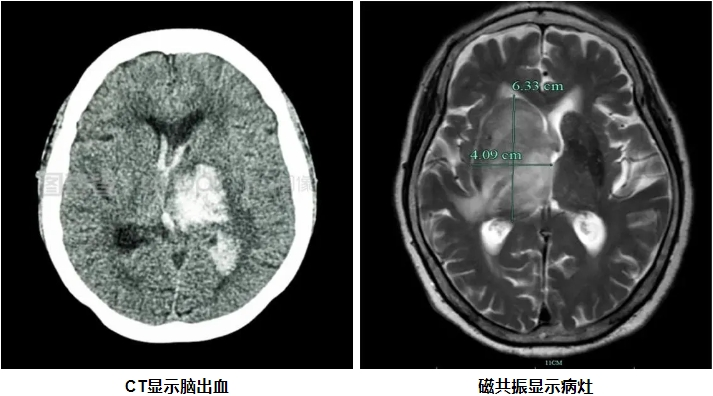

CT与磁共振成像原理及特点 CT检查是利用X线穿透人体后,通过探测器收集数据,再由计算机重建出人体内部结构的图像。它具有成像速度快、密度分辨率高的特点,能够快速发现颅内出血、骨折等病变。然而,CT检查存在一定的局限性,比如对软组织的分辨率较低,且由于颅骨的干扰,后脑病变的显示效果不佳。如果要显示脑血管,需要注射造影剂。 磁共振成像是一种无辐射的检查技术,通过强大的磁场和无线电波脉冲,利用人体内不同组织的磁化反应来成像。它具有多方位、多参数成像的特点,能够提供丰富的组织对比度和详细的解剖信息。磁共振检查在软组织分辨率、图像立体观和抗骨性干扰等方面具有显著优势。 磁共振对后脑病灶显示的优势 后颅窝是脑部的一个重要区域,包括小脑、脑干等重要结构。由于其位置较深,且周围有颅骨的遮挡,CT检查在显示后颅窝病变时往往受到限制。而磁共振检查则能够很好地弥补这一不足。此外,磁共振对软组织的分辨率极高,能够清晰显示小脑、脑干等部位的病变,如脑梗死、肿瘤、脑干病变等。此外磁共振DWI序列能在脑梗死后发生后数分钟就可以发现病灶,而CT需要发病后6-24小时才能发现病灶。尤其是症状表现为头晕,眩晕的患者推荐磁共振检查。 图例: 72岁,男性,突发右侧偏瘫,左侧面瘫,言语含混6小时,CT未见异常,磁共振显示左侧桥脑腹外侧脑梗死。 磁共振评估颅内血管的优势 磁共振血管成像(MRA)是磁共振技术在血管检查中的重要应用。它是一种无创性检查方法,无需注射造影剂,即可获得高分辨率的血管影像。这使得MRA特别适合长期随访的患者以及对造影剂过敏的人群。MRA能够清晰显示颅内动脉的狭窄、闭塞、动脉瘤、动静脉畸形等病变。

虽然 CT 和磁共振在脑部检查各有各的厉害之处,但它们谁也代替不了谁。CT 检查速度快,要是遇到急性脑出血这种紧急情况,能快速诊断,在急诊的时候,还能作为分科的依据。而磁共振在分辨软组织、查看后颅窝病变、评估颅内血管这些方面,优势特别明显。所以在看病的时候,医生会根据患者的具体病情,还有检查的目的,综合考虑要不要做 CT 和磁共振,这样才能得到更全面、更准确的诊断信息。 总的来说,磁共振成像在查看后颅窝病灶和评估颅内血管方面,优势非常突出,是检查脑部疾病必不可少的重要手段。要是遇到一些复杂的脑部病变,只做 CT 检查可能没办法明确诊断,这时候做磁共振,就能给医生提供更详细、更准确的信息,帮助医生制定出更合理的治疗方案。